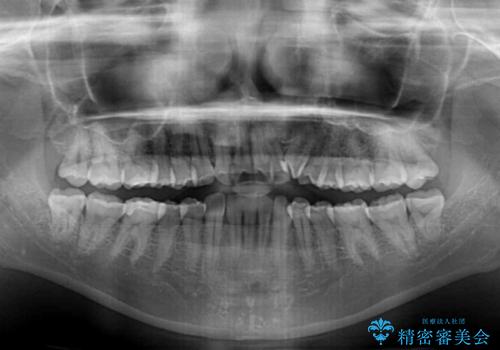

診査を行ったところ、下顎前歯が1本欠損しており、下顎歯列が上顎よりも小さくなっていることで、上顎にデコボコが生じていました。

口元を見ると抜歯をして突出感を改善するような状態ではなかったため、上顎歯列のデコボコを整えて、歯列全体を後方に移動させることでバランスを取ることとしました。